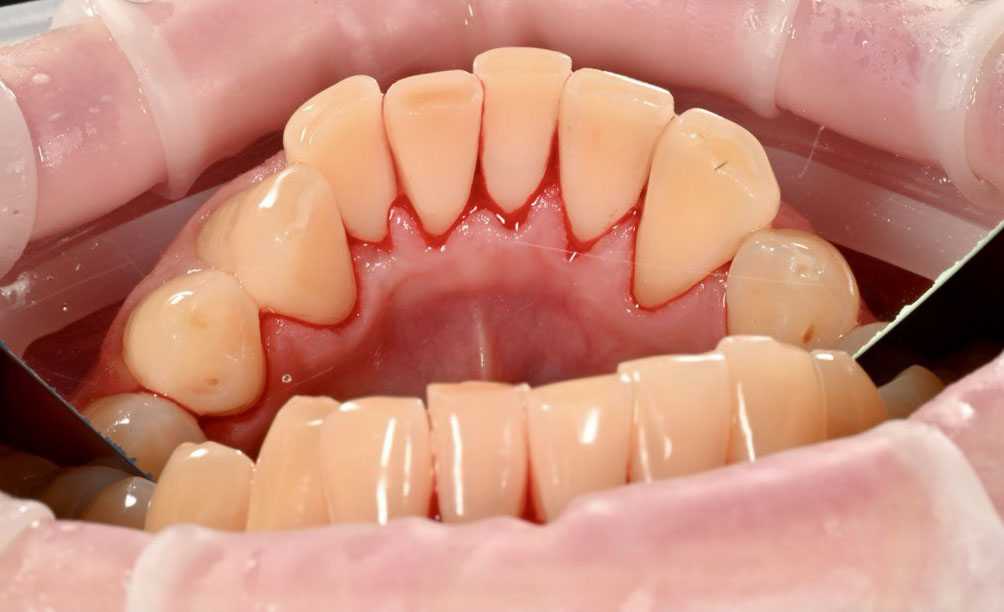

Пациент обратился в клинику с жалобами на кровоточивость дёсен во время ежедневной чистки зубов. Также отмечал ощущение налёта и недостаточной чистоты, несмотря на регулярный домашний уход.

Во время осмотра было выявлено:

• выраженное скопление пигментированного налёта

• наличие зубодесневых отложений, провоцирующих воспаление дёсен

Такие изменения часто становятся причиной кровоточивости, неприятных ощущений и могут привести к заболеваниям дёсен при отсутствии профессиональной гигиены.